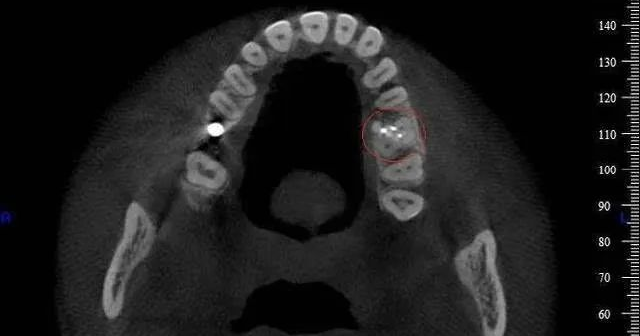

(1)多生牙的定位:

口腔ct怎么拍摄【专科天地】没有口腔CT,你根本不会想到自己的牙齿长得多“奇葩”!_https://www.jmylbn.com_新闻资讯_第14张